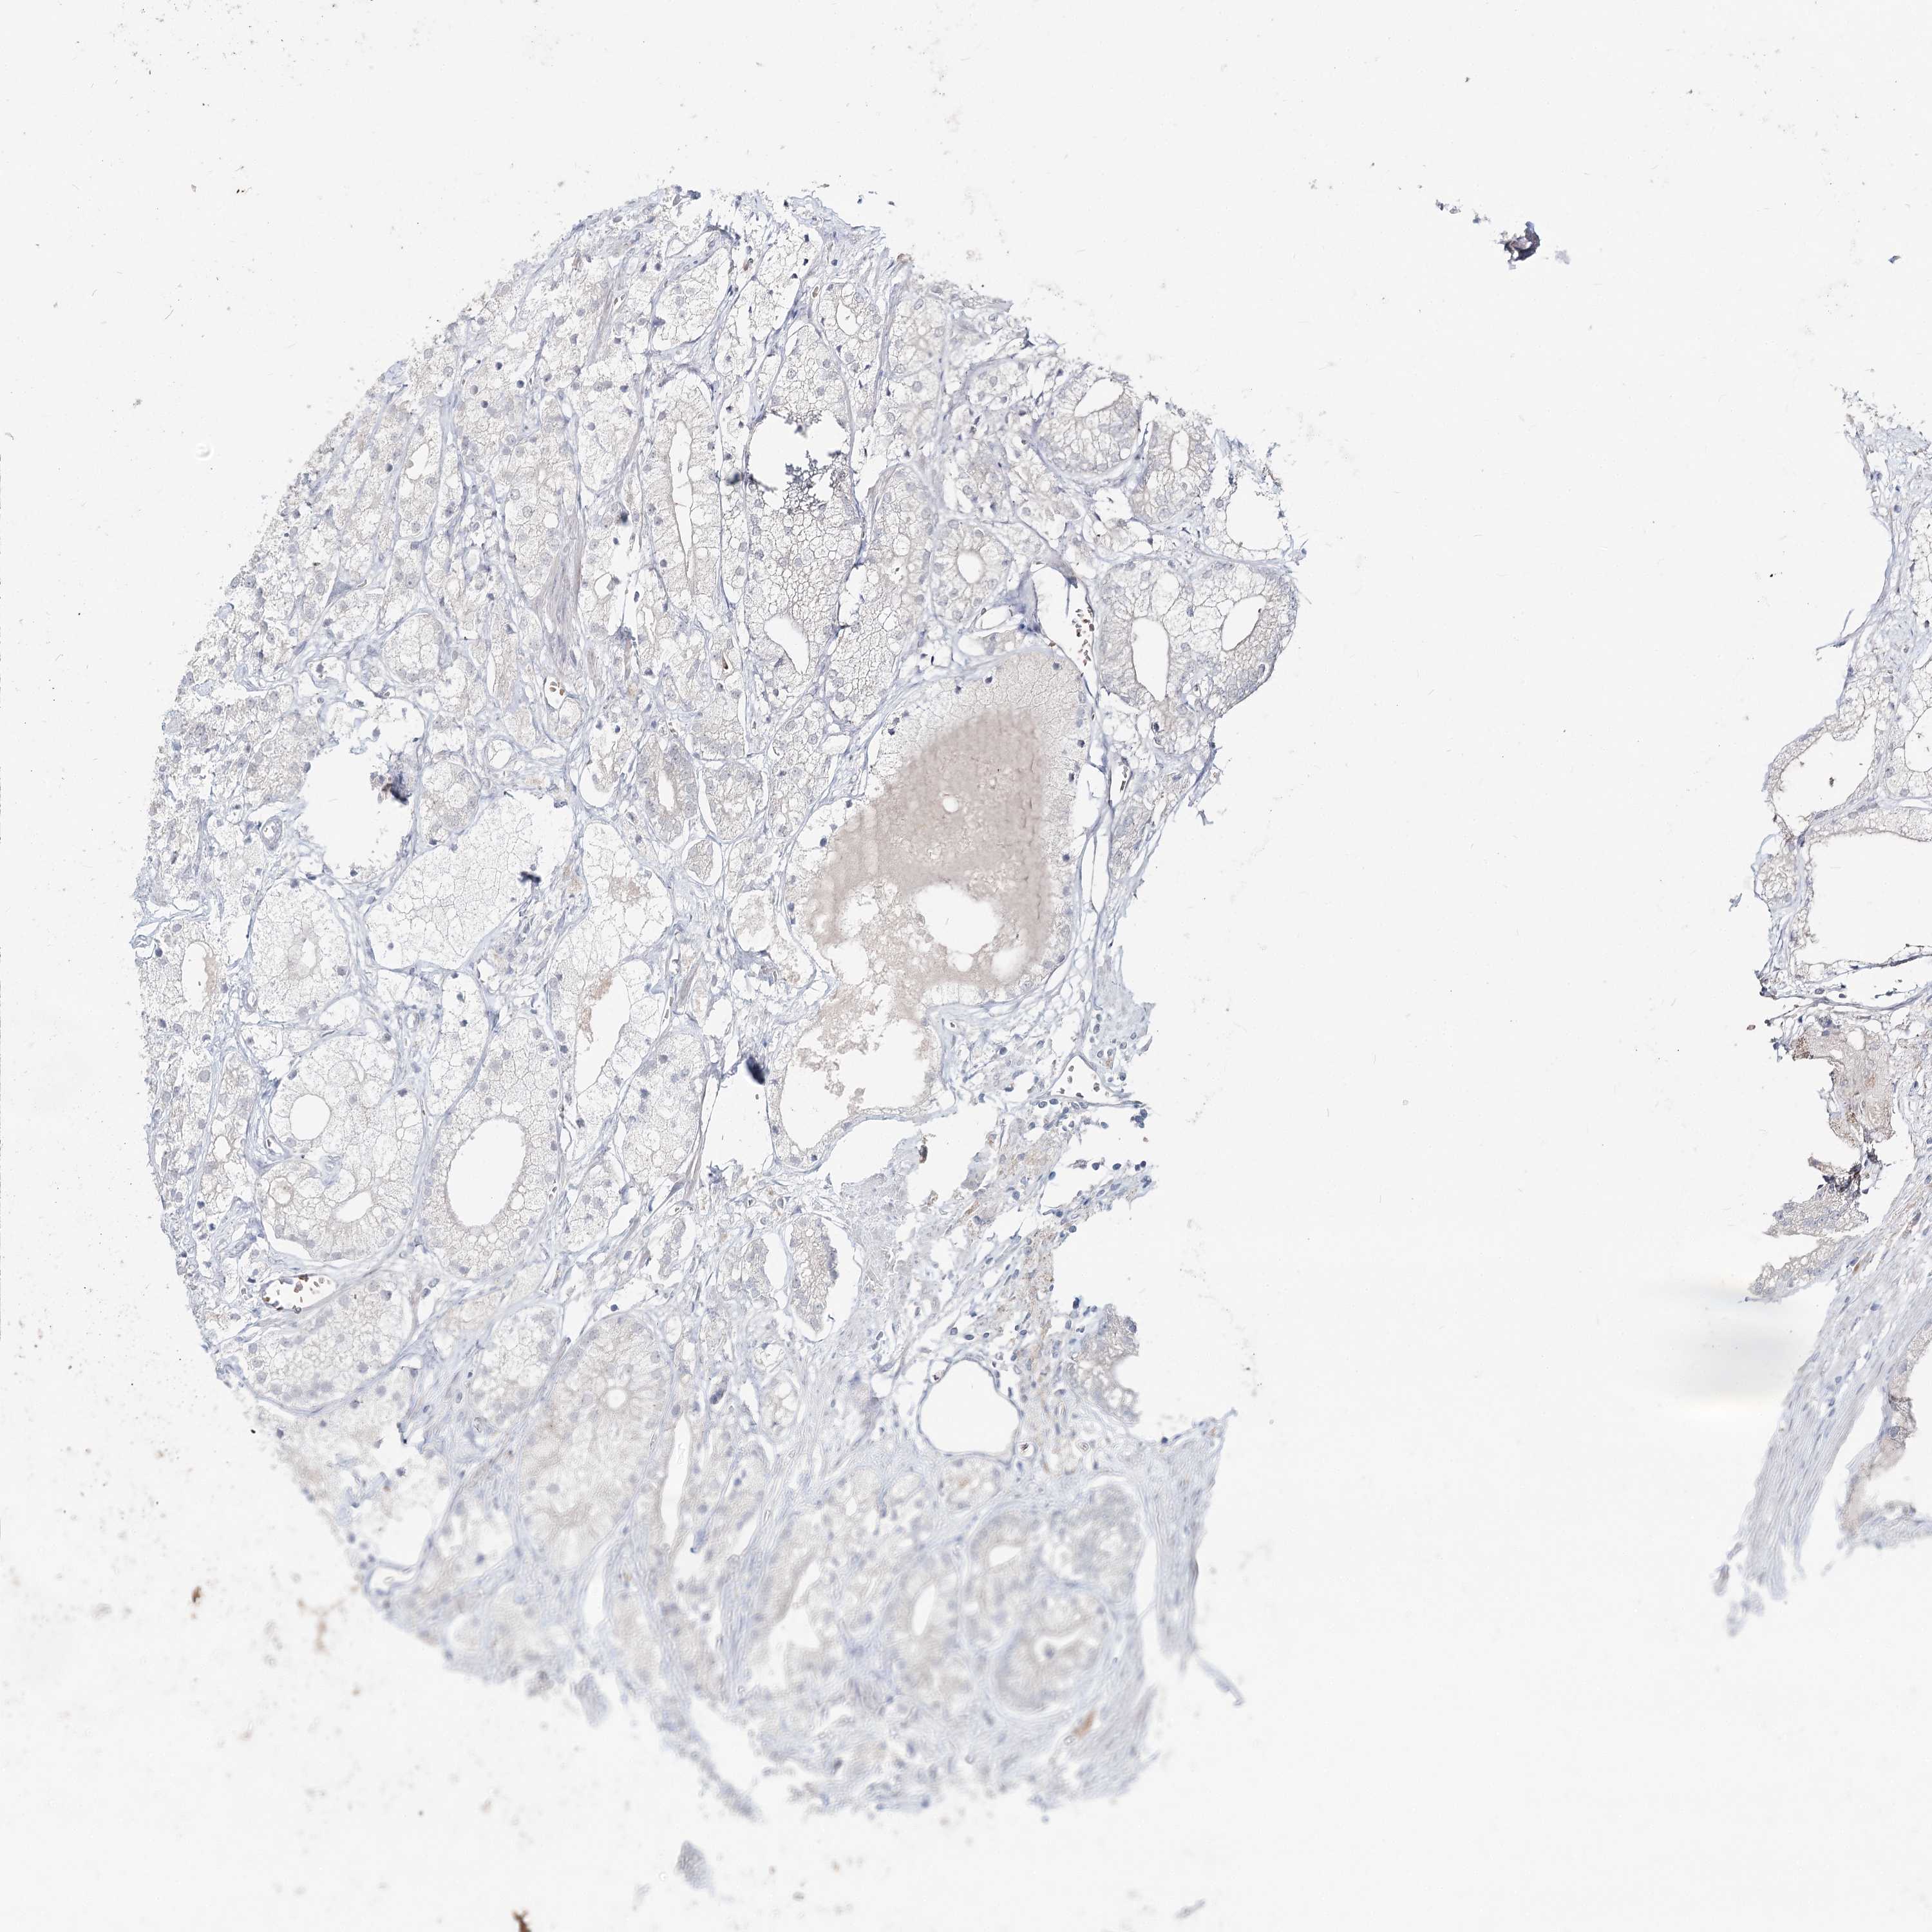

PROSTATE CANCER - Protein expressioni

A mouse-over function shows sample information and annotation data. Click on an image to view it in a full screen mode. Samples can be filtered based on level of antibody staining by selecting one or several of the following categories: high, medium, low and not detected. The assay and annotation is described here.

Antibody stainingi

Antibody staining in the annotated cell types in the current human tissue is reported as not detected, low, medium, or high, based on conventional immunohistochemistry profiling in selected tissues. This score is based on the combination of the staining intensity and fraction of stained cells.

Each image is clickable and will lead to virtual microscopy that enables deeper exploration of all samples and also displays staining intensity scores, fraction scores and subcellular localization as well as patient and tissue information for each sample.

Antibody HPA032114

Antibody HPA057352

Antibody CAB034296

Staining

High

Medium

Low

Not detected

Intensity

Strong

Moderate

Weak

Negative

Quantity

>75%

75%-25%

<25%

None

Location

Nuclear

Cytoplasmic/membranous

Cytoplasmic/membranous,nuclear

Adenocarcinoma, NOS

Adenocarcinoma, High grade

Adenocarcinoma, Low grade